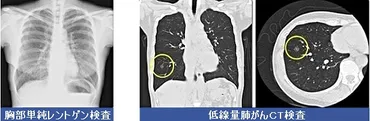

診断には、CTスキャン、MRI、PETスキャン、生検などが用いられます。